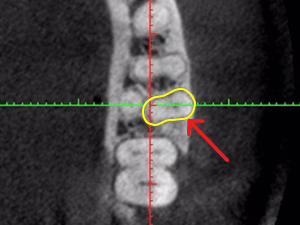

大阪の根管治療の専門の先生がこの方法を発明しまして、以下の写真の様にマイナスドライバーを2本使ってテコの原理を用い金属の土台を除去します。

80%以上この方法で金属の土台は除去することが可能です。